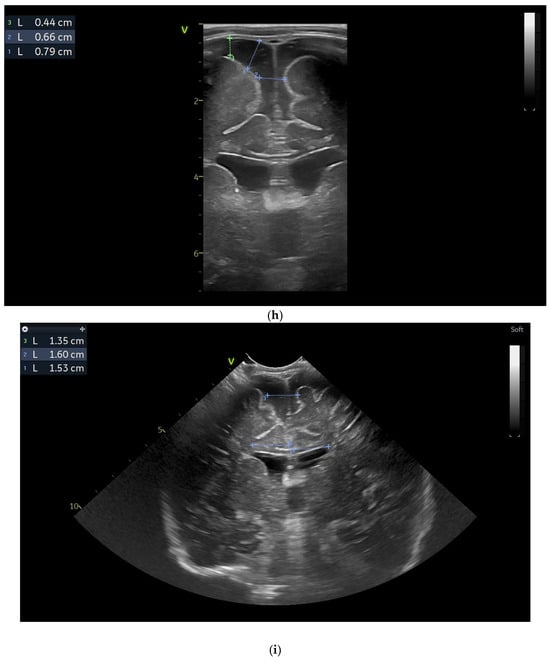

At two minutes of life, with a heart rate of 120 bpm, chest compressions were discontinued, and the patient continued to be ventilated via endotracheal tube. The newborn was then transported while ventilated in an incubator to the neonatal intensive care unit (NICU), where SIMV ventilation was initiated, along with surfactant administration. The day one cranial ultrasound (CUS) showed bilateral periventricular hyperechoic images and enlargement of the lateral ventricles (Figure 1a–d).

Figure 1.

(a) Cranial ultrasound. Day one. Coronal view. D1 and D2—Levine index measurement. D3—cisterna magna measurement (personal image collection). (b) Cranial ultrasound. Day one. Coronal view. Lateral ventricle dilatation. LV—lateral ventricles. PC—plexus choroidus (personal image collection). (c) Cranial ultrasound. Day one. Right lateral ventricle. D1—thalamo-occipital distance measurement. Yellow arrow—parieto-occipital hyperechoic images (personal image collection). (d) Cranial ultrasound. Day one. Left lateral ventricle. D1—thalamo-occipital distance measurement. Yellow arrow—parieto-occipital hyperechoic images (personal image collection). (e) Day three. Cranial ultrasound. Coronal view. Ventricular asymmetry. D1 and D2—Levine index measurement. D3 and D4—anterior horn width measurement. Left ventricular enlargement (personal image collection). (f) Day three. Cranial ultrasound. Coronal view. Ventricular asymmetry (left ventricle larger than right ventricle). Yellow arrows—periventricular hyperechoic images are becoming more visible (personal image collection). (g) Day three. Cranial ultrasound. Coronal view. Linear probe. Ventricular asymmetry (left ventricle larger than right ventricle). LV—lateral ventricle (anterior horns). IHF—interhemispheric fissure. Yellow arrows—hyperechoic images in the thalamic-caudate groove (suggestive of a germinal matrix hemorrhage) (personal image collection). (h,i) Day 13. First LP. Cranial ultrasound. Coronal view. Up (before LP). D1 and D2—Levine index measurement. LV—lateral ventricles (anterior horns). IHF—interhemispheric fissure. Down (after LP). Dimensions of ventricles were reduced after LP. D1 and D2—anterior horn width. LV—lateral ventricles (anterior horns). OH—occipital horn (personal image collection). (j,k) Day 19. Second LP. Cranial ultrasound. Coronal view. Dimensions of ventricles were reduced after LP. Left (before LP). D1 and D2—Levine index measurement. Right (after LP). D1 and D2—Levine index measurement (personal image collection). (l) Day 39. Cranial ultrasound. Coronal view. Yellow arrows—periventricular cystic hyperechoic images—suggesting periventricular leukomalacia (cystic form) (personal image collection). (m) Head circumference-for-age. “X” symbols represent the measurements performed from birth and follow-up examinations. Initially, the head circumference was under the curve (personal image collection) [28].

After 72 h, the patient was extubated. The CUS showed bilateral IVH (grade III Volpe/Papile) (Figure 1e,f).

During the in-stay, two lumbar punctures (LP) were performed (Figure 1h–k).

In evolution, our patient presented bilateral ventricular dilatation and bilateral PVL (cystic form, grade III) (Figure 1l). The neurological assessment established eye contact and the infant could hold its head during the traction maneuver. The passive tone assessment showed the “scarf sign”, with the elbow at the midline bilaterally and a popliteal angle of 90°. The deep tendon reflexes (DTRs) were symmetrical.

Clinically, hypertonicity of the legs and axial muscles was present. At the one-year follow-up examination, the patient showed developmental delay and strabismus. At the three-year follow-up examination, cerebral palsy could be observed, which was bilateral and spastic with a predominance of the legs. The classification according to the Gross Motor Function Classification System (GMFCS) was grade III.